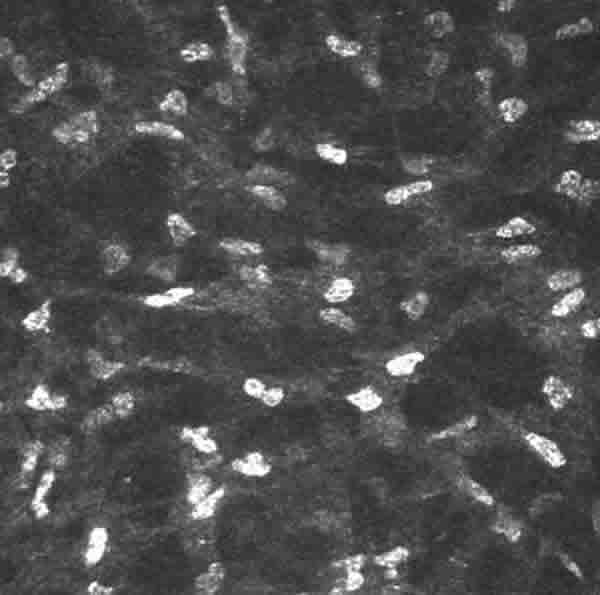

Estroma profundo: Concentración de queratocitos mayor que en estroma medio y menor que en estroma anterior (fig. 9).

Fig. 9. Estroma posterior en el que aumenta el número de queratocitos con

respecto al estroma medio.